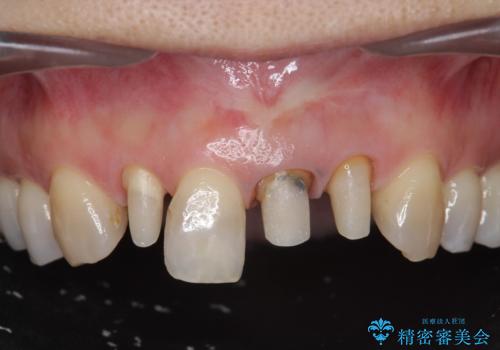

前歯のフチが黒いのが気になる 前歯のセラミック治療

- 前歯のクラウンの歯肉の位置が年々変化し、歯ぐきのフチが黒くなってしまった、綺麗にしたいと希望されて来院されました。

装着されているセラミッククラウンを除去したのち、現在の歯ぐきのラインにしっかりと合う精度の高いオールセラミッククラウンを作製していきます。